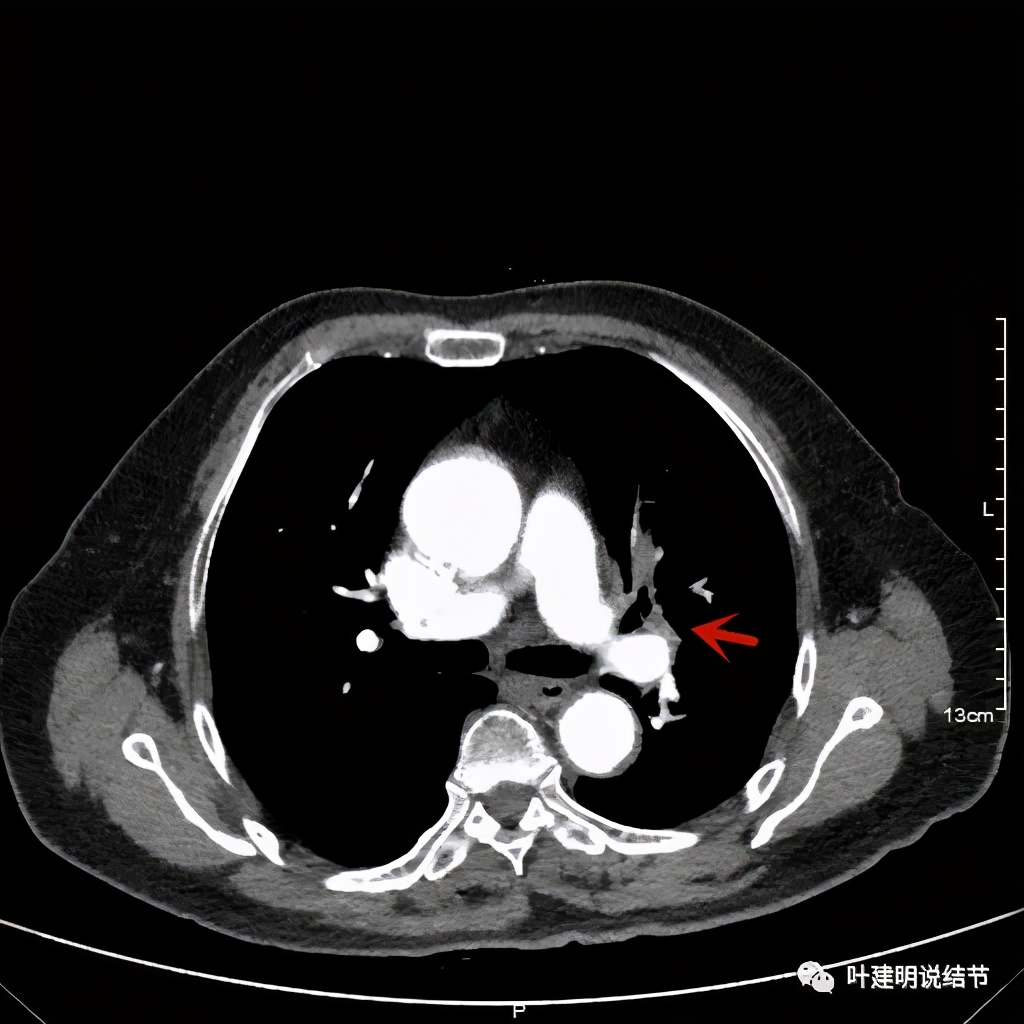

上图示肿瘤部位仍与肺动脉关系密切,似乎未能脱开,红色示肿瘤处

我样的治疗效果,显然超出了我们之前的预期,那么接下来拟选择行手术治疗,初定左上叶袖式肺叶切除加淋巴结清扫,但因为肺门区仍有软组织影,与肺动脉的关系仍密切,肿瘤与肺动脉间能否游离开来还是未知数,但至少得努力争取,鉴于患者年纪虽大,肺功能指标尚可,血气分析也基本正常,所以与患方沟通后确定行手术探查,但也也说明有万一全肺切除的可能(虽然这种可能性较小)。